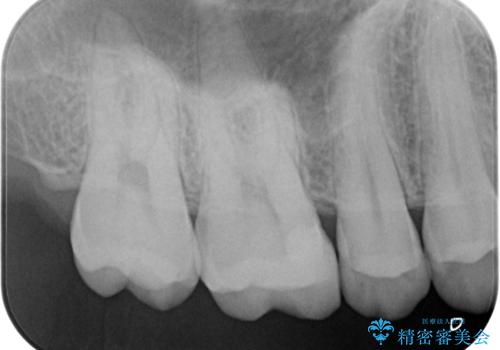

白くて適合の良い詰め物が入りました。

e-maxインレーは保険のインレーに比べて虫歯の再発のリスクが低くなります。